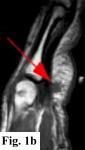

MRI FINDINGS:   MRI was performed on AIC's high-field 1.5 Tesla short-bore Siemens Symphony scanner using a small flexible surface coil. Fig. 1a is a high-resolution coronal DESS, Fig. 1b a sagittal T1 weighted, Fig. 1c a sagittal turbo STIR, and Fig. 1d an axial T1 weighted. They demonstrate a 5x5x7 mm nodule in the volar aspect of the hand at the level of the 4th MCP joint inseparable from the flexor digitorum superficialis tendon (arrows) with some adjacent soft tissue edema. The underlying tendon and bones are otherwise intact.

DIFFERENTIAL DIAGNOSIS:   Based on the MRI findings the DDX includes a benign soft tissue tumor such as a xanthoma, fibroma, hemangioma, neuroma or a lesion related to the tendon sheath such as a giant cell tumor of the tendon sheath or tendinous xanthoma. An inflammatory node was also in the differential. It does not have the MRI characteristics of a cyst or ganglion.

SURGICAL-PATHOLOGIC DIAGNOSIS:   The patient was taken to surgery at LCH by Dr. Rahmati and a "rather solid round mass attached to the volar aspect of the 4th tendon sheath" (arrows in Fig. 2a-b) was excised measuring about 4x4x3 mm. Pathology at LCH revealed a "grayish-white somewhat nodular smooth soft tissue measuring 9x8x5 mm" with histopathologic "features in favor of a giant cell tumor of tendon sheath" interpreted as benign.